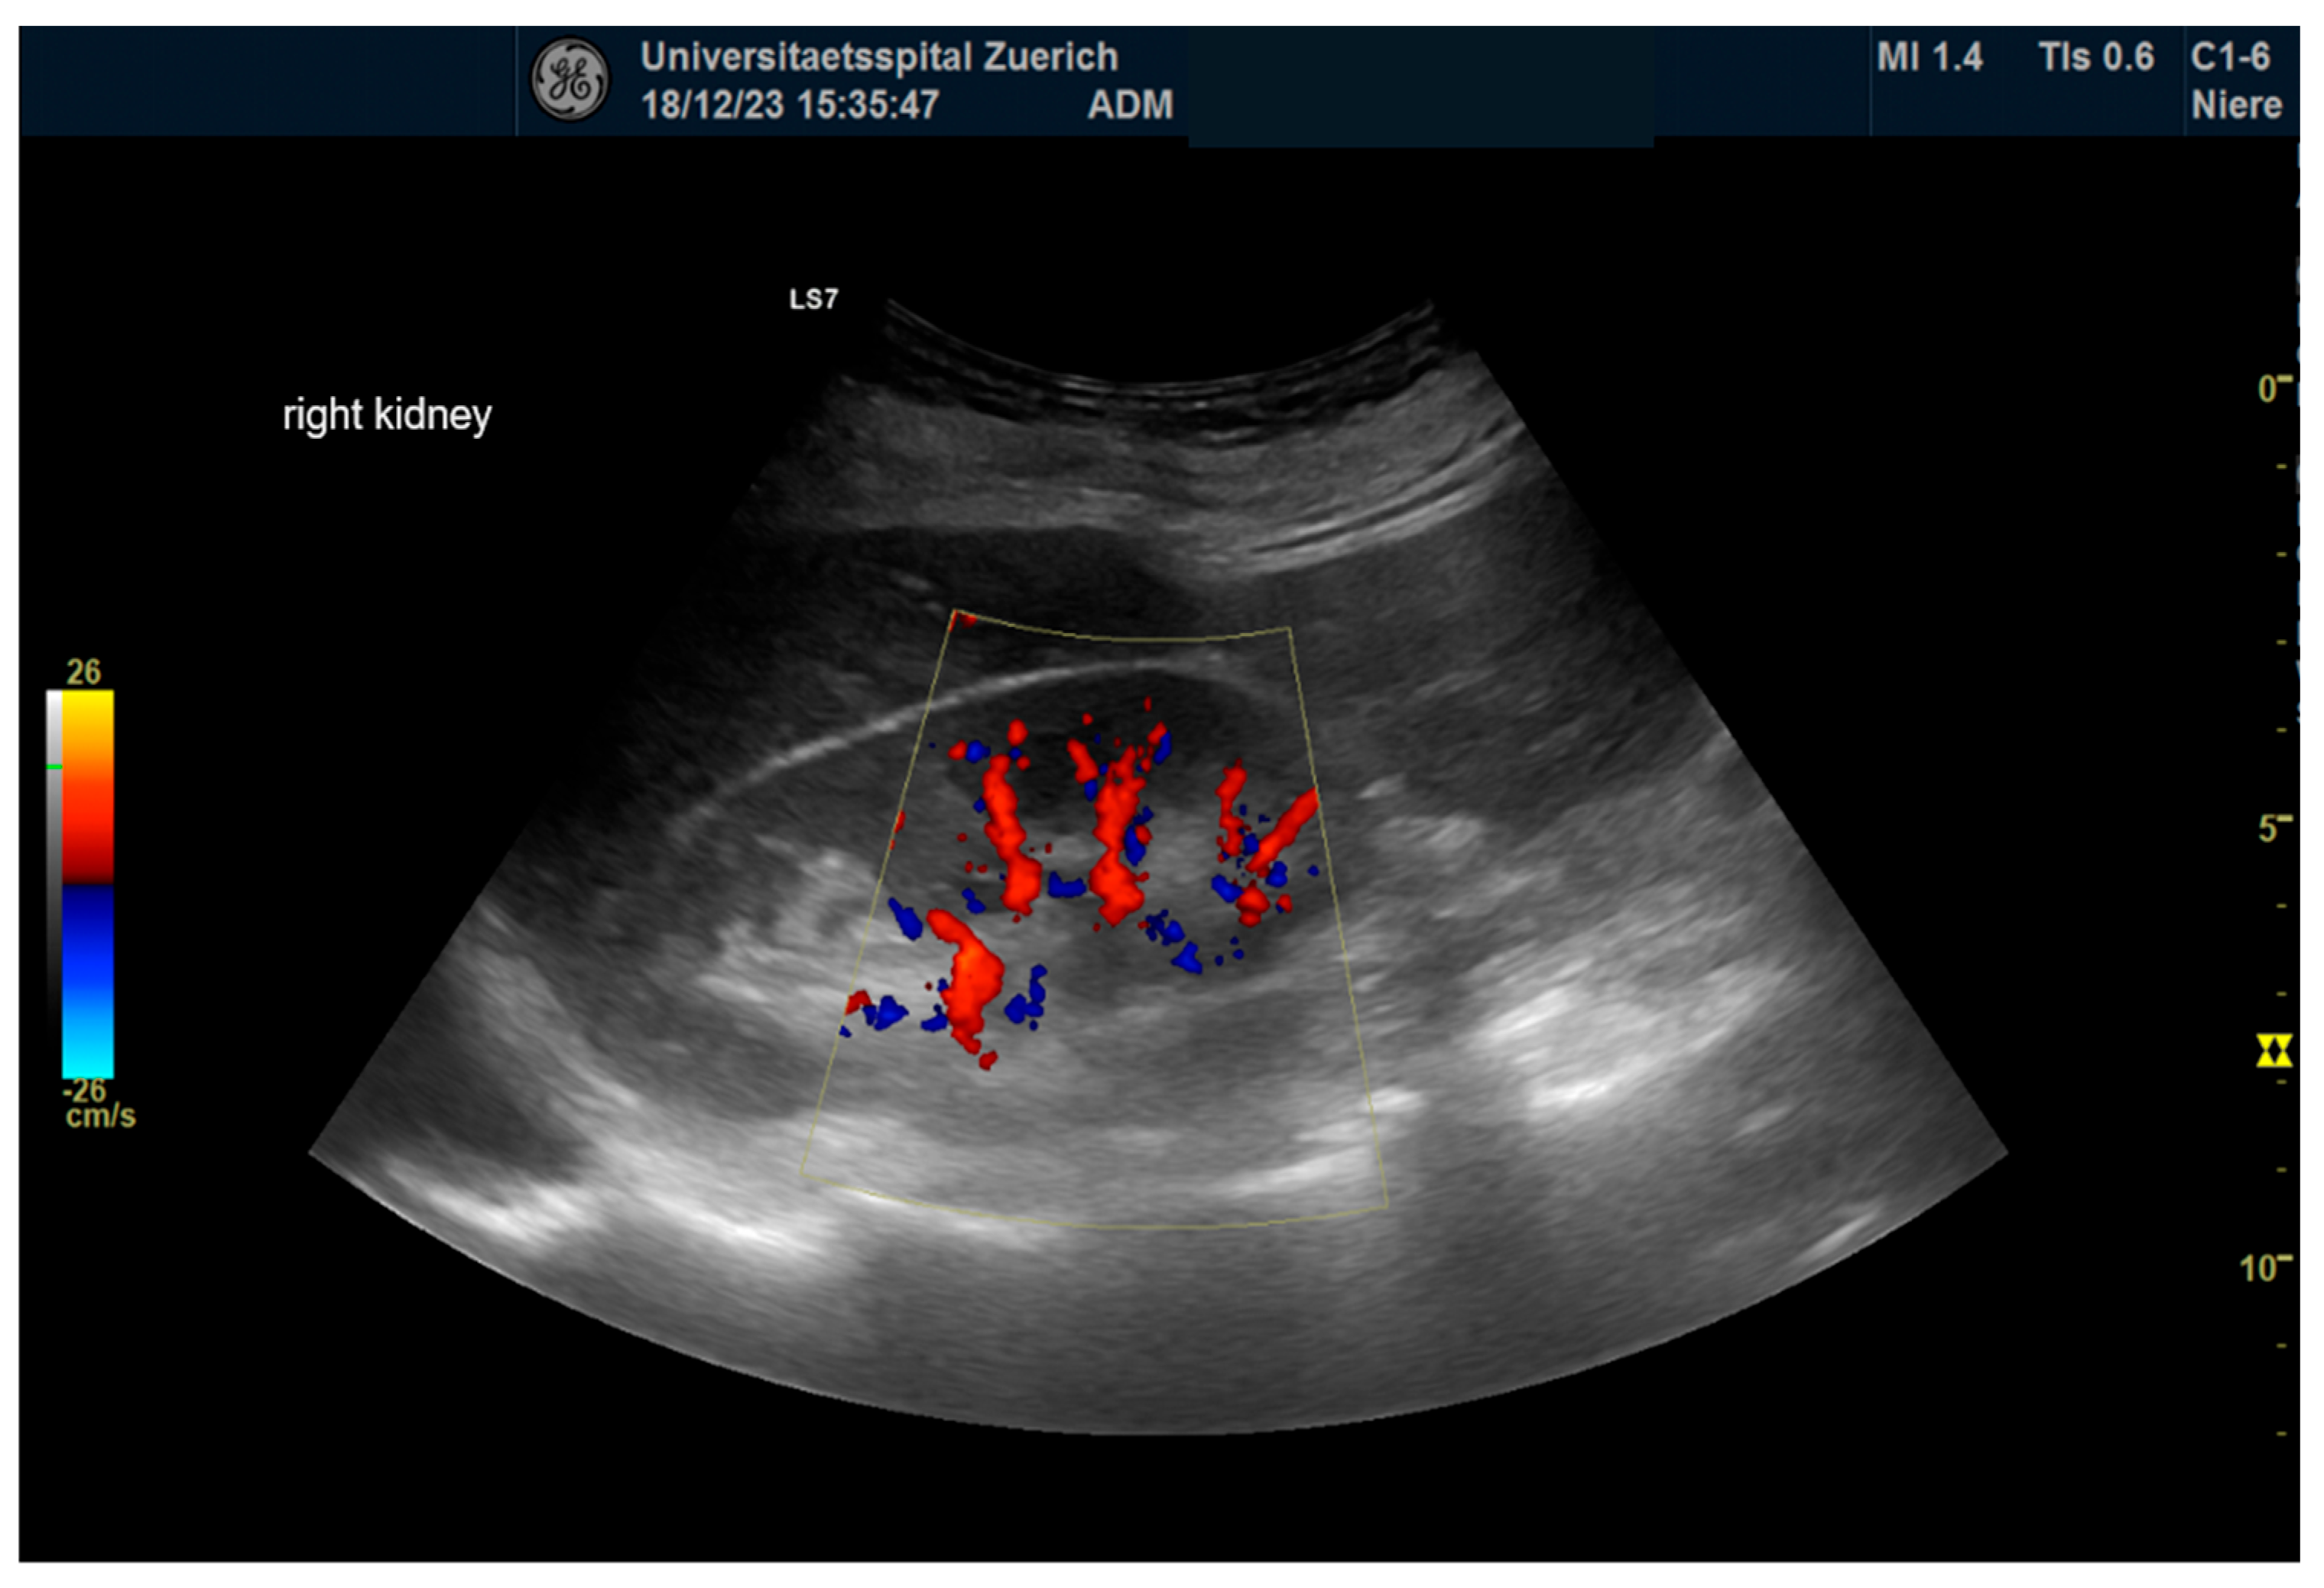

2.4. Ultrasonography

| Renal Parameters (n = 64) | Pre-Operative | Post-Operative | p |

| RRI | 0.66 ± 0.06 | 0.67 ± 0.07 | ns |